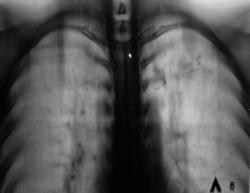

Мне кажется, что импрессионного перелома бугорка (повреждение Хилл-Сакса) здесь нет. При данном повреждении импрессия более выражена. Типичный перелом Хилл-Сакса выглядит примерно так.